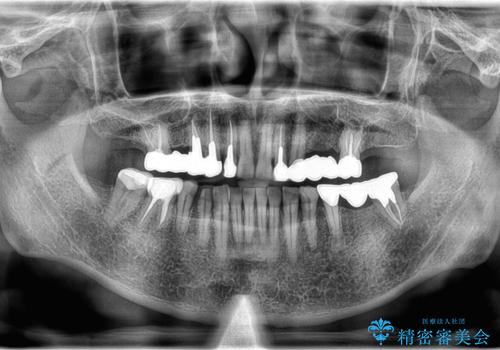

- 右上奥歯の歯肉から出血があり異和感をおぼえ来院された患者様です。

歯周治療と補綴治療を行いました。

以前の被せ物を除去し、仮歯に変えてすぐに異和感がとれました。

歯周治療を行い、歯肉が引き締まってから補綴治療しました。